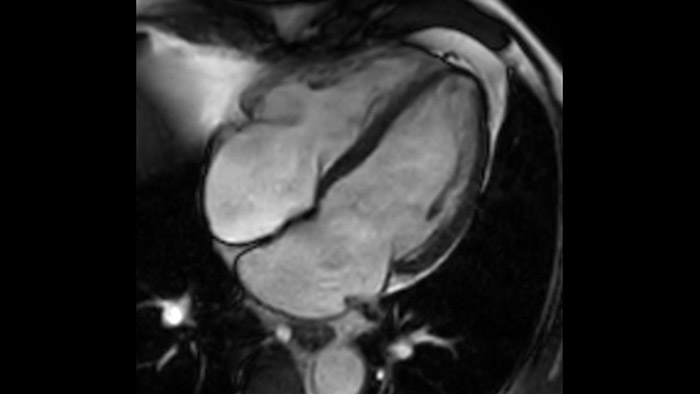

La diagnostica tradizionale non offre la visibilità necessaria per vedere gli effetti di un trattamento cardiaco o individuare disfunzioni prima che si verifichino i sintomi. Combinando la sequenza di acquisizione MRI Fast-SENC di Philips con lo strumento di analisi MyoStrain di Myocardial Solutions, i lievi cambiamenti precoci nella funzione cardiaca possono essere misurati direttamente.

La diagnostica odierna spesso non è in grado di rilevare le disfunzioni cardiache fino a quando non si manifestano sintomi. MyoStrain valuta la deformazione del miocardio in 48 segmenti cardiaci e fornisce ai medici uno strumento diagnostico utile per identificare con anticipo la disfunzione funzionale prima che il cuore nel suo complesso sia compromesso.